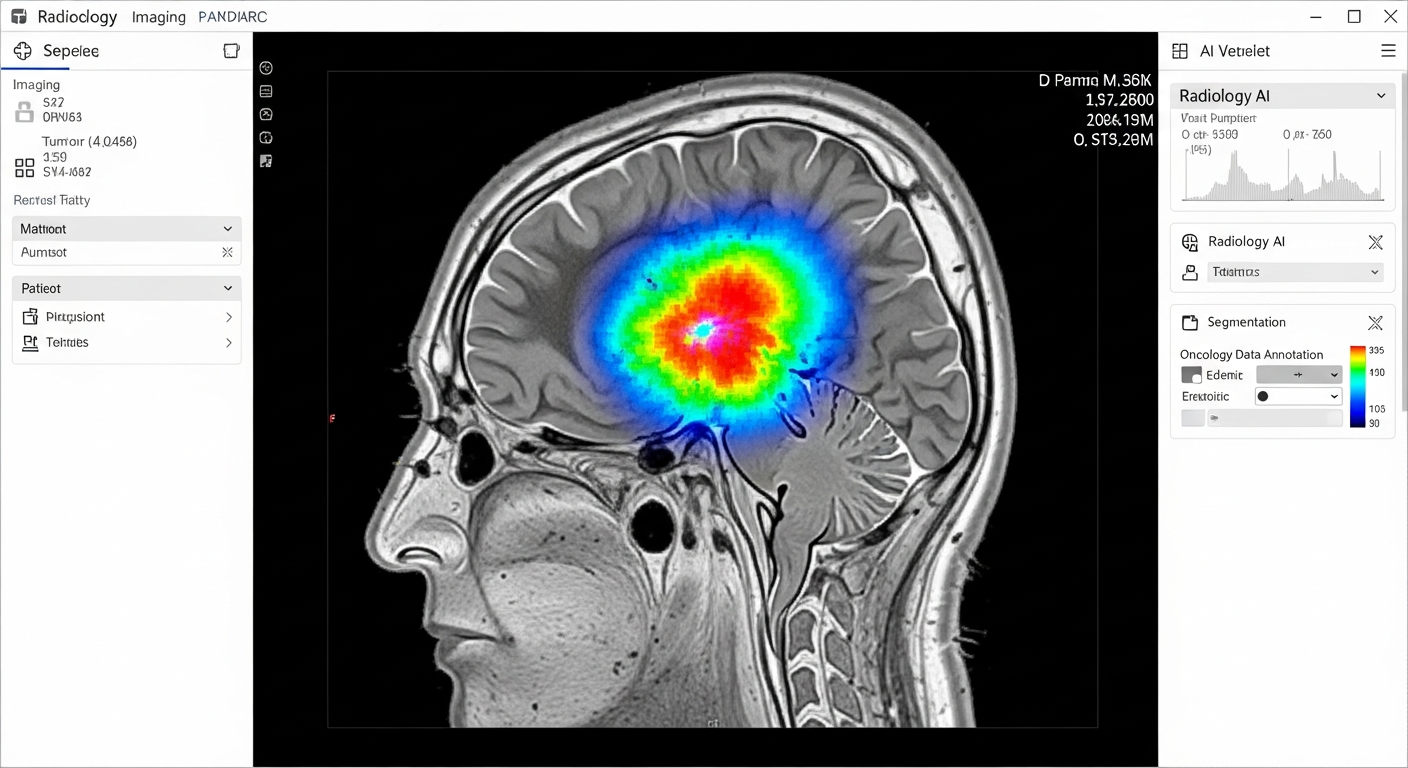

Data Annotation Use Cases in FDA Compliance & Support

Annotation & labeling of data can serve a variety of purposes within FDA Compliance & Support, from enabling critical computer vision to gaining a better sense of the surroundings for AI initiatives.

The following use cases provide more insight into how our data annotation & labeling expertise can benefit your FDA Compliance & Support operations: